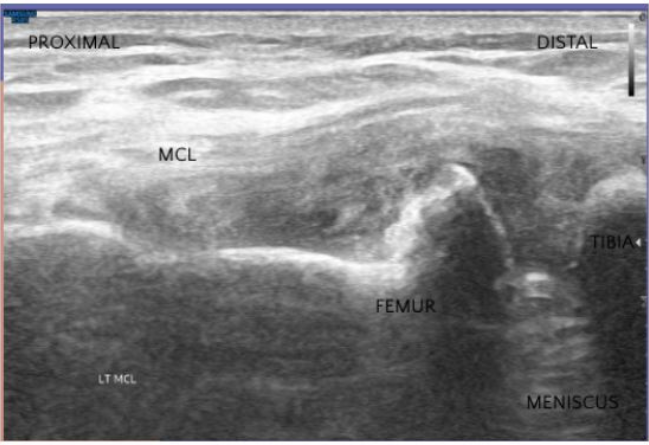

• Medial Collateral Ligament (MCL)

Using diagnostic ultrasound and image-guided injections, we ensure highly precise biologic placement within the knee joint and surrounding structures. This accuracy leads to more effective outcomes, reduced pain, and improved long-term function.